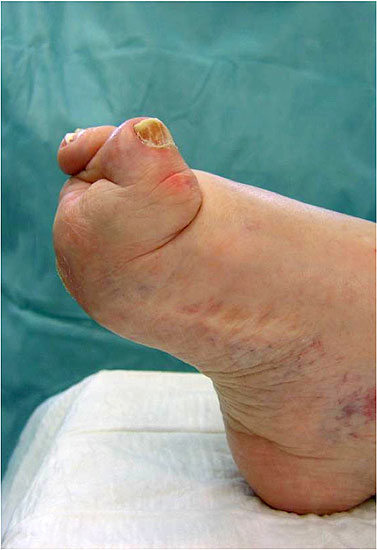

Spitzhohlfuß

• diverse neurogene und nicht neurogene Erkrankungen (Abb. 6 und 7)

• Druckdolenzen unter allen Metatarsaleköpfen

• Unelastisches Gangbild durch mangelnden Fersenkontakt in der Standphase, „Stolzieren“

Zusätzlich bei Progredienz der neurologischen Grunderkrankung:

• Abkippen des Fusses in die Inversions- oder Eversionsdeformität des Rückfusses bei muskulären Dysbalance